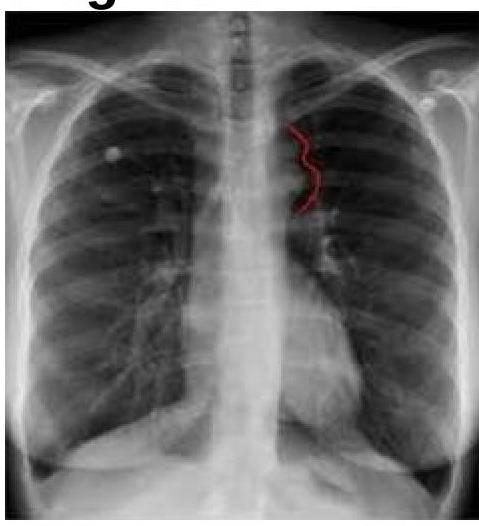

PA view of chest X-ray is given here. What is the diagnosis?

Explanation: ***Right Pneumothorax with left tracheal shift*** - The image shows a large **radiolucency (black area) on the right side** of the chest, indicative of **air in the pleural space**, consistent with a **right-sided pneumothorax**. - The **trachea is shifted towards the left** (away from the pneumothorax), which is the **expected finding** in pneumothorax due to increased pressure in the right pleural space pushing mediastinal structures to the contralateral side. - In pneumothorax, the trachea and mediastinum shift **away from** the affected side due to the pressure effect of air accumulation in the pleural cavity. - This **contralateral tracheal deviation** is a classic radiological sign of pneumothorax and helps confirm the diagnosis. *Right Pneumothorax with right tracheal shift* - While the **right pneumothorax** is correctly identified, the tracheal shift direction is incorrect. - In pneumothorax, the trachea shifts **away from** the affected side (contralateral), not toward it (ipsilateral). - **Ipsilateral tracheal shift** would suggest volume loss (atelectasis) or lung collapse, not pneumothorax alone. *Left Pneumothorax with right tracheal shift* - The pneumothorax is clearly on the **right side**, not the left. - The radiolucency and absent lung markings are visible on the right hemithorax. - A left pneumothorax would show these findings on the left side. *Left Pneumothorax with left tracheal shift* - There is **no pneumothorax on the left side** of the chest. - The left lung shows normal vascular markings and no evidence of pleural air. - This combination would be medically implausible as it suggests pneumothorax with ipsilateral shift.